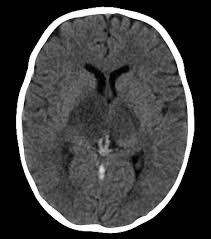

Common subtypes include transverse sinus thrombosis and superior sagittal sinus. What causes cerebral venous sinus thrombosis? Magnetic resonance imaging of cerebral venous sinus thrombosis. Aha scientific statements ⅲ venous thrombosis ⅲ sinus thrombosis, intracranial ⅲ brain infarction figure 1. Cerebral venous sinus thrombosis in early pregnancy: The cavernous sinus is one of the several cerebral veins and cavernous sinus thrombosis is a specific type of cerebral venous (sinus) thrombosis. Cerebral venous thrombosis (cvt) or cerebral venous sinus thrombosis (cvst): Cochrane database syst rev 2011; Cerebral venous and sinus thrombosis (cvst) is a rare disease responsible for less than 1% from the total of avc causes (bajenaru, 2010). Thrombosis of cerebral veins and venous sinuses is a rare disease, which accounts for less than 1% of all cases of stroke. The venous circulation of the brain is done. Risk factors, presentation, diagnosis and outcome. See that article for a discussion of that specific clinical entity.

Magnetic resonance imaging of cerebral venous sinus thrombosis. (iii) clinical and radiological features of brain lesions in csvt compared with arterial stroke, and (iv) a low threshold for ct or mr venography in children with acute neurological symptoms is essential. Can cerebral venous sinus thrombosis be prevented? Thrombosis of cerebral veins and venous sinuses is a rare disease, which accounts for less than 1% of all cases of stroke. Cerebral venous thrombosis (cvt) is an uncommon disorder in the general population. A thrombotic obstruction of the cerebral veins and/or related anatomical structures (dural sinuses) which drain blood from the brain. Cerebral venous thrombosis accounts for less than 1 % of all cases of stroke worldwide. A case report and review of the literature. Cerebral venous and sinus thrombosis (cvst) is a rare disease responsible for less than 1% from the total of avc causes (bajenaru, 2010). Cerebral venous sinus thrombosis occurs when a blood clot forms in the brain's venous sinuses. Cerebral venous thrombosis (cvt) refers to occlusion of venous channels in the cranial cavity, including dural venous thrombosis, cortical vein although not used routinely in clinical practice, whole brain ct perfusion may assist in establishing the diagnosis of cvt by detecting perfusion. Common subtypes include transverse sinus thrombosis and superior sagittal sinus. Cerebral venous thrombosis (cvt) or cerebral venous sinus thrombosis (cvst):